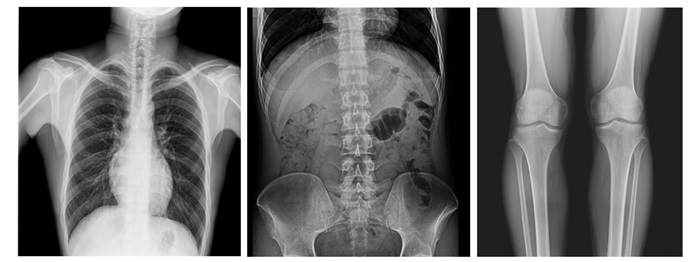

17×17英寸大幅面成像,一次曝光即可實現(xiàn)胸部、腹部全覆蓋,無需移動即可觀察整個動態(tài)過程,避免拖尾、噪聲對圖像的影響,避免漏診誤診;最高30幀/s采集幀率,動態(tài)影像更流暢,便于使醫(yī)生觀察細(xì)微病變,提高診斷的準(zhǔn)確性。